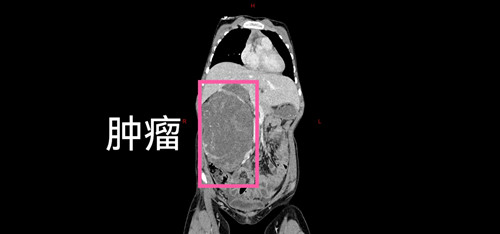

抱着一线希望,家人带着女孩来到了山西省儿童医院普外科。入院后,完善各项检查,结果比预想的更为复杂:初步诊断为节细胞神经母细胞瘤,且已伴有腹膜后广泛转移和盆腔转移。影像学显示,主肿瘤与腹主动脉、下腔静脉紧密粘连,右侧肾动脉甚至穿行于瘤体之中,而盆腔的转移灶与主瘤体不相连。这意味着,手术将如同在血管的“丛林中排雷”,稍有不慎,后果不堪设想。

然而在打开腹腔的那一刻,即使这些经验丰富的医护人员都倒吸一口凉气。由于肿瘤生长时间太长,它已经像一棵根系发达的老树,与周围的正常组织“长”在了一起。特别是与下腔静脉、腹主动脉以及脊柱的粘连,达到了密不可分的程度。每一步分离,都如同在悬崖边行走,需要极致的精细和稳定。